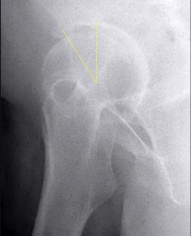

A 13-year-old overweight male presents with an acute exacerbation of chronic right groin and knee pain. He walks with an externally rotated gait. Radiographs confirm a severe Slipped Capital Femoral Epiphysis (SCFE).

Pathophysiologically, the slippage in SCFE occurs primarily through which specific histological zone of the proximal femoral physis?

Explanation

Slipped Capital Femoral Epiphysis (SCFE) typically occurs due to mechanical shear forces across a weakened physis during the adolescent growth spurt. Histologically and biomechanically, the weakest layer of the growth plate is the zone of hypertrophy. The slippage classically occurs through this layer because the chondrocytes are enlarged, and the extracellular matrix is sparse compared to the reserve or proliferative zones, making it highly susceptible to shear stress.